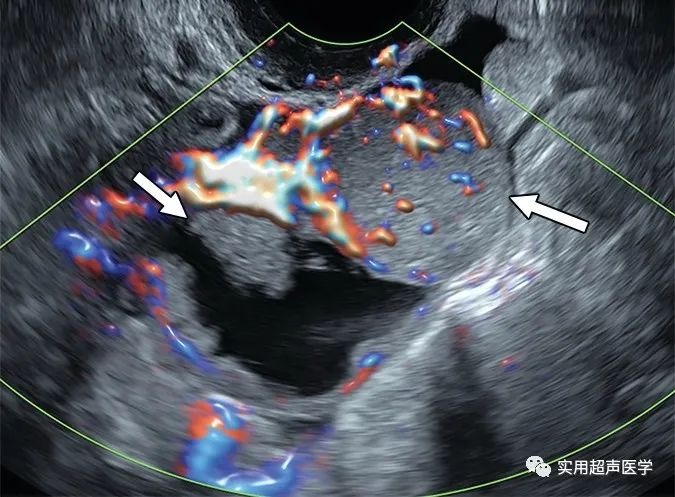

67岁女性,彩色多普勒超声图像显示多房囊性病变,伴有大而实心的血管化成分(箭头),被证明是高级别浆液性输卵管癌。颜色评分 (CS) 对于具有实体成分的多房囊性病变的适当卵巢-附件报告和数据系统 (O-RADS) 分类非常重要。彩色多普勒成像显示非常强的血流 (CS 4),符合 O-RADS 5 类病变。大小与具有这些特征的病变的风险分层无关。状投影和非状实性成分之间的区别与多房囊性病变的 O-RADS 分类无关。